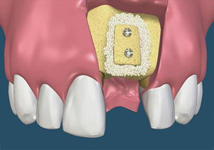

Novinkou v augmentačních metodách, kterou jako první v České republice používáme v našem zařízení je ultrazvuková metoda pomocí polylaktidové membrány - SonicWeld Rx®, kterou zavedl do implantologie v roce 2009 Dr. Dr. G.Iglhaut (Memmingen, Německo).

Jedná se o augmentační metodu při dostavbách kosti a defektech kosti horní a dolní čelisti.

SonicWeld Rx